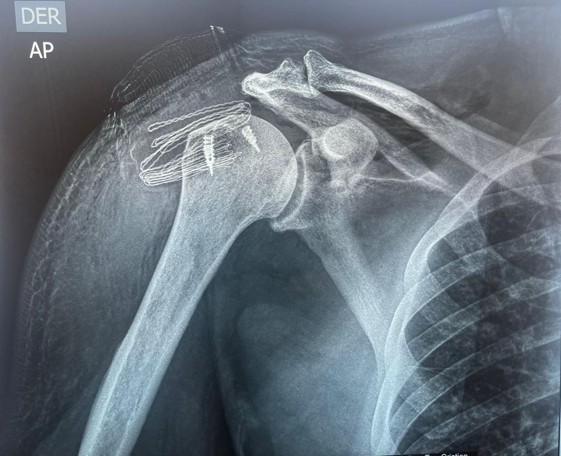

Patologías de Hombro

El hombro es una articulación compleja y la más móvil del cuerpo, compuesta por cuatro articulaciones: la glenohumeral (cabeza del húmero con la escápula), la escapulotorácica (escápula sobre la pared torácica), y las dos articulaciones de la clavícula (acromioclavicular y esternoclavicular). Cualquier de ellas puede causar dolor. En más del 90% de los casos, el dolor se debe a patologías de los tendones del manguito rotador. La continua movilidad del hombro, junto con actividades físicas y laborales, acentúa el desgaste y la rotura de estos tendones. El aumento de la actividad física y deportiva también ha incrementado las lesiones traumáticas.

Lesiones del Manguito Rotador: Los tendones del hombro, en forma de cintas anchas, rodean la cabeza del húmero como una «manga» (de ahí el nombre de manguito rotador). Su función principal no es levantar el brazo (que es del deltoides), sino realizar los giros o rotaciones. El supraespinoso es uno de estos tendones superiores y es el más afectado por problemas inflamatorios y roturas. El tendón de la porción larga del bíceps (con forma de cordón) también es comúnmente afectado. Estos tendones se deslizan bajo un arco formado por el acromion (prolongación de la escápula) y un ligamento que lo une a la coracoides. El roce continuo y repetido de los tendones bajo este arco óseo es un factor clave en la aparición de inflamación (tendinitis y tendinosis) y roturas posteriores. El diagnóstico de estas lesiones se sospecha por la exploración física y se confirma con ecografía y, especialmente, Resonancia Magnética (RM). Las RMs de última generación (3 Tesla) ofrecen un altísimo nivel de seguridad diagnóstica.

Roturas de los Tendones del Hombro: Son la consecuencia de las tendinitis y tendinosis por la misma causa de roce continuo. El supraespinoso es el tendón que se rompe con mayor frecuencia, pero también pueden afectarse el subescapular y el infraespinoso. Muchas roturas combinan dos o más tendones y, a menudo, también la porción larga del bíceps. El síntoma constante es el dolor, pero también hay una pérdida de fuerza de rotación del/los tendón/es afectados. Estas roturas son degenerativas y no cicatrizan por sí solas. Por ello, el tratamiento aconsejado es quirúrgico (artroscopia), que requiere poca estancia hospitalaria pero un periodo de rehabilitación de al menos 3 o 4 meses. Factores adversos para la recuperación son las roturas grandes y de larga evolución, y el consumo de tabaco.

Inestabilidad del Hombro o Luxación Recidivante: El hombro es la articulación que se luxa con mayor frecuencia debido a que la gran cabeza del húmero se articula con una pequeña superficie de la escápula. Cuando el hombro se luxa, rompe estructuras como el labrum, la cápsula y los ligamentos. También se produce una lesión en los huesos que chocan (lesión de Hill-Sachs). Tras la reducción (colocación del hombro en su lugar), se inmoviliza el brazo durante 4 semanas para permitir la cicatrización de las estructuras. Sin embargo, la cicatrización no siempre es adecuada, ya que los tejidos pueden quedar elongados. Por ello, es frecuente que el hombro se luxe de nuevo y con mayor frecuencia (luxación recidivante), especialmente en pacientes jóvenes que practican deportes de contacto. El tratamiento de los primeros episodios consiste en la reducción, inmovilización y rehabilitación. Pero si se repite, el tratamiento debe ser quirúrgico. Mediante artroscopia, reparamos las estructuras lesionadas (labrum, cápsula, ligamentos, lesión ósea) con un solo día de ingreso, seguido de un período de rehabilitación de 4-6 meses. Las luxaciones también pueden ocurrir en personas mayores, pero en estos casos suelen afectar los tendones del manguito rotador. La necesidad de tratamiento quirúrgico por artroscopia dependerá del tamaño de la rotura y de la recurrencia de los episodios.